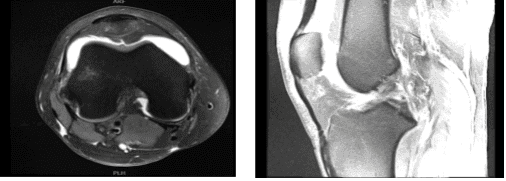

MRI results were presented and reviewed by the doctor, the result was discussed, the Ligaments are a full-thickness ACL tear with progression since the prior study. No posterolateral corner injury. The PCL, MCL and lateral collateral ligament complex and the extensor mechanism are Intact.

The lateral compartment is the complex tearing of the lateral meniscus posterior horn and horizontal tear of the anterior horn. There is partial-thickness cartilage loss and deep chondral fissuring along the central weight bearing aspect of the lateral femoral condyle with adjacent marrow edema indicative of bone contusions versus stress reaction.

There is mild partial-thickness cartilage loss along the posterior aspect of the lateral tibial plateau. The Medial Compartment is a longitudinal peripheral tearing of the medial meniscus at the posterior meniscocapsular junction on series 5 images 27-32.

There is focal full-thickness chondral fissuring along the inner aspect of the medial femoral condyle with faint stress reaction adjacent to the fissure. The patellar and trochlear cartilage are preserved.

The Tibial and femoral bone contusion pattern indicative of a recent anterior tibial translation. There is a large joint effusion. Muscles/Tendons are Intact, while the Neurovascular Structures and Subcutaneous Tissues are Unremarkable.

It has full-thickness ACL tear with bone contusion pattern indicative of a recent anterior tibial translation. The ACL tear has now progressed to full-thickness and is worse compared to the prior study.

The tearing of the medial and lateral meniscus, progressive in severity since the prior study. And slight partial-thickness cartilage loss and fissuring as discussed above. It also has large joint effusion, increased in size.

MRI-3T Right knee non-contrast